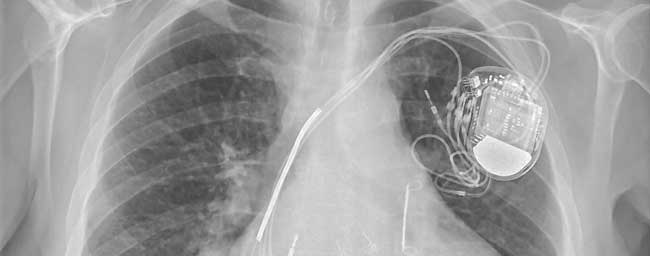

L’histoire de la cardiologie est jalonnée de progrès thérapeutiques médicaux et instrumentaux : la stimulation cardiaque fait partie de ces innovations qui ont révolutionné le pronostic des troubles conductifs intracardiaques. Les stimulateurs cardiaques ont acquis au fils des ans un degré de fiabilité et de sophistication qui n’exclue toutefois pas un suivi régulier.